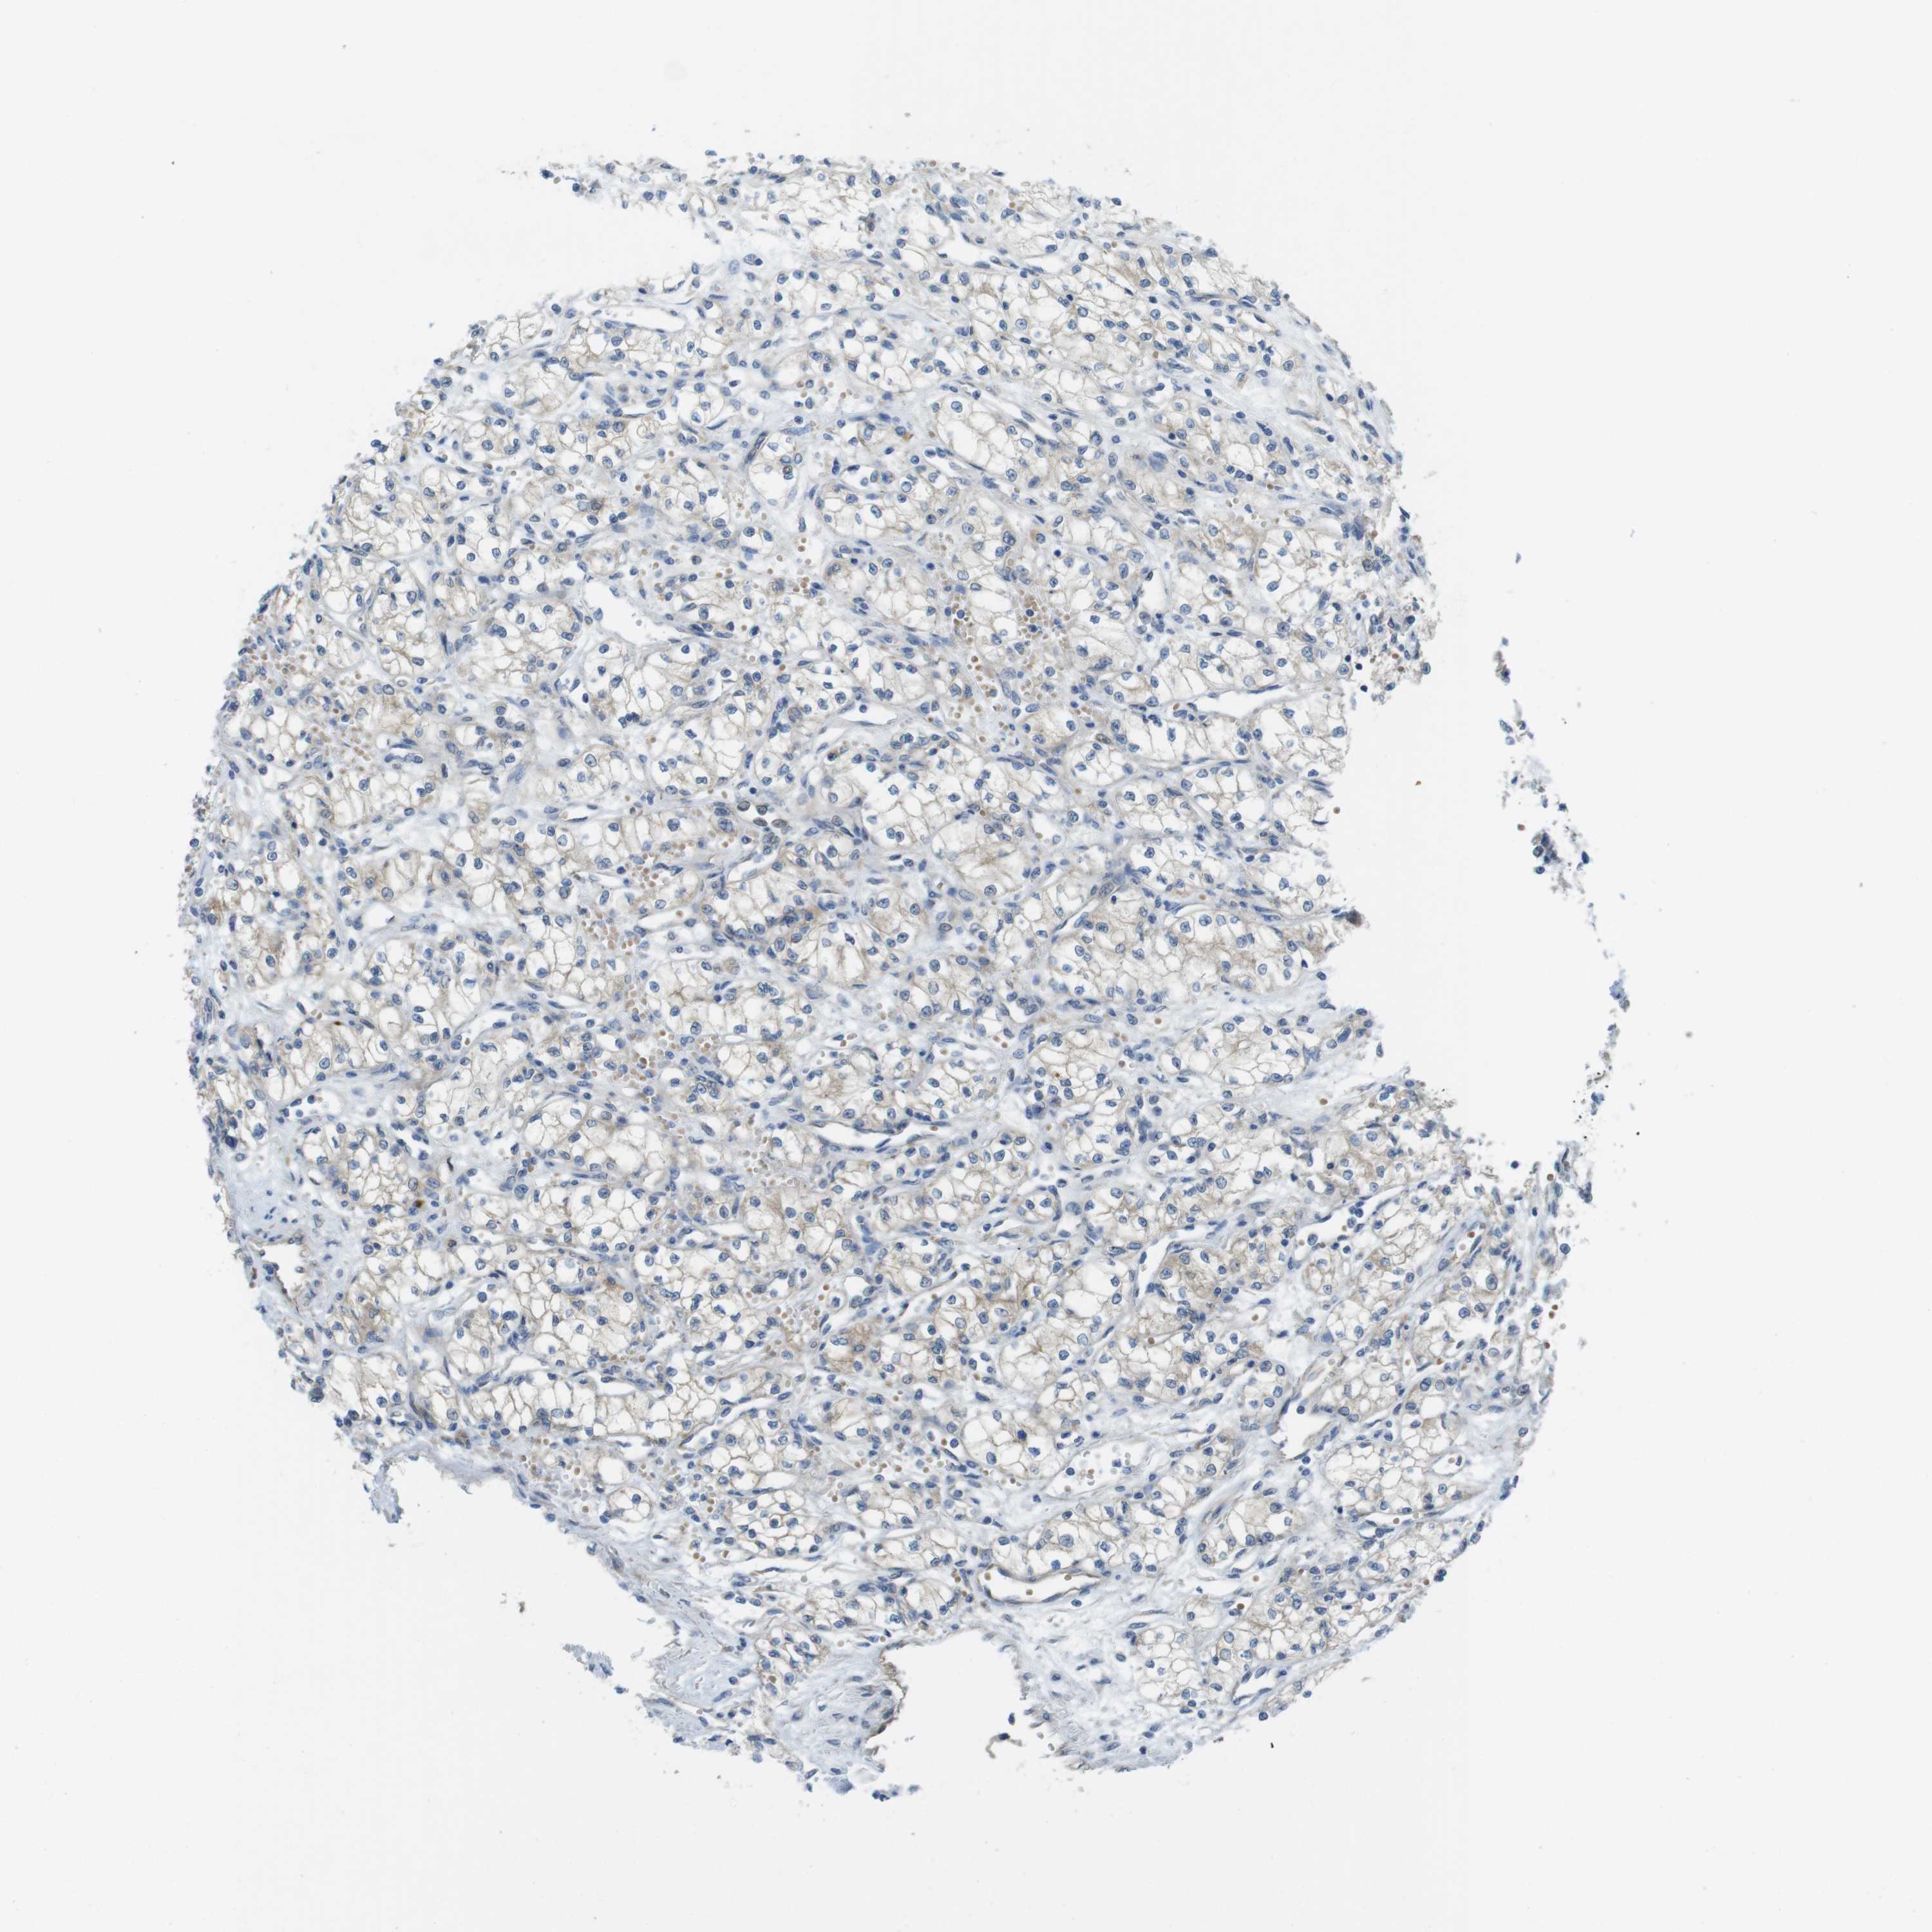

CANCER RENAL CANCER Show tissue menu

KICH TCGA KIRC TCGA KIRC VALIDATION KIRP TCGA PROTEIN RCC CPTAC PROTEIN EXPRESSION

Renal cancer

Kidney chromophobe

KIDNEY CHROMOPHOBE (TCGA) - Interactive survival scatter ploti

TMEM234 is not prognostic in Kidney Chromophobe (TCGA)